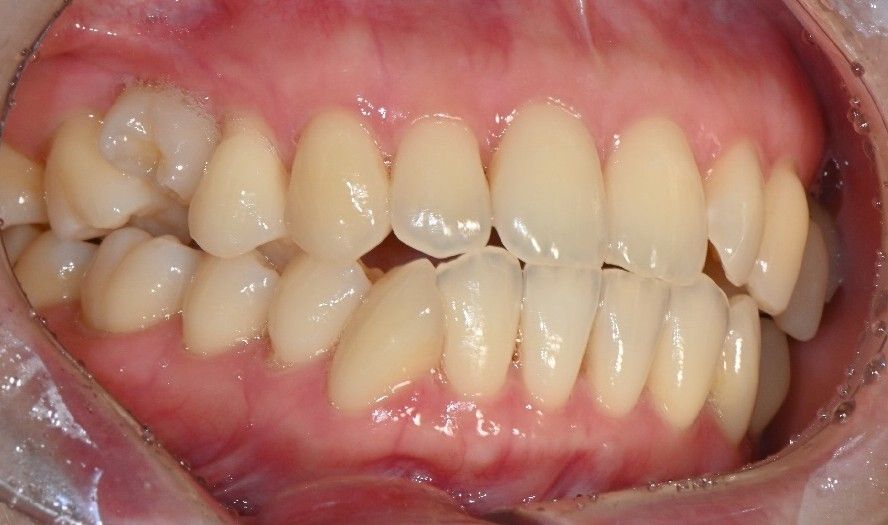

우측 상단 어금니 시림 증상 질문입니다.

오늘 시린증상이 심해져서 다시 동네치과를 가니 여전히 겉으로는 문제가 없고. 다만 어금니에 충격이 가해지고 치아 신경에 문제가 생긴거라면 신경치료가 필요할수는 있다. 다만 턱을 크게 벌려야 하기 때문에 턱부터 치료해야한다. 라는 소견만 듣고 왔습니다.

첫번째 갔었던 병원은 치주인대에 무리가 간것같으니 쉬게하면 나아질거다 라고 했었고요.

• 2번 째 사진